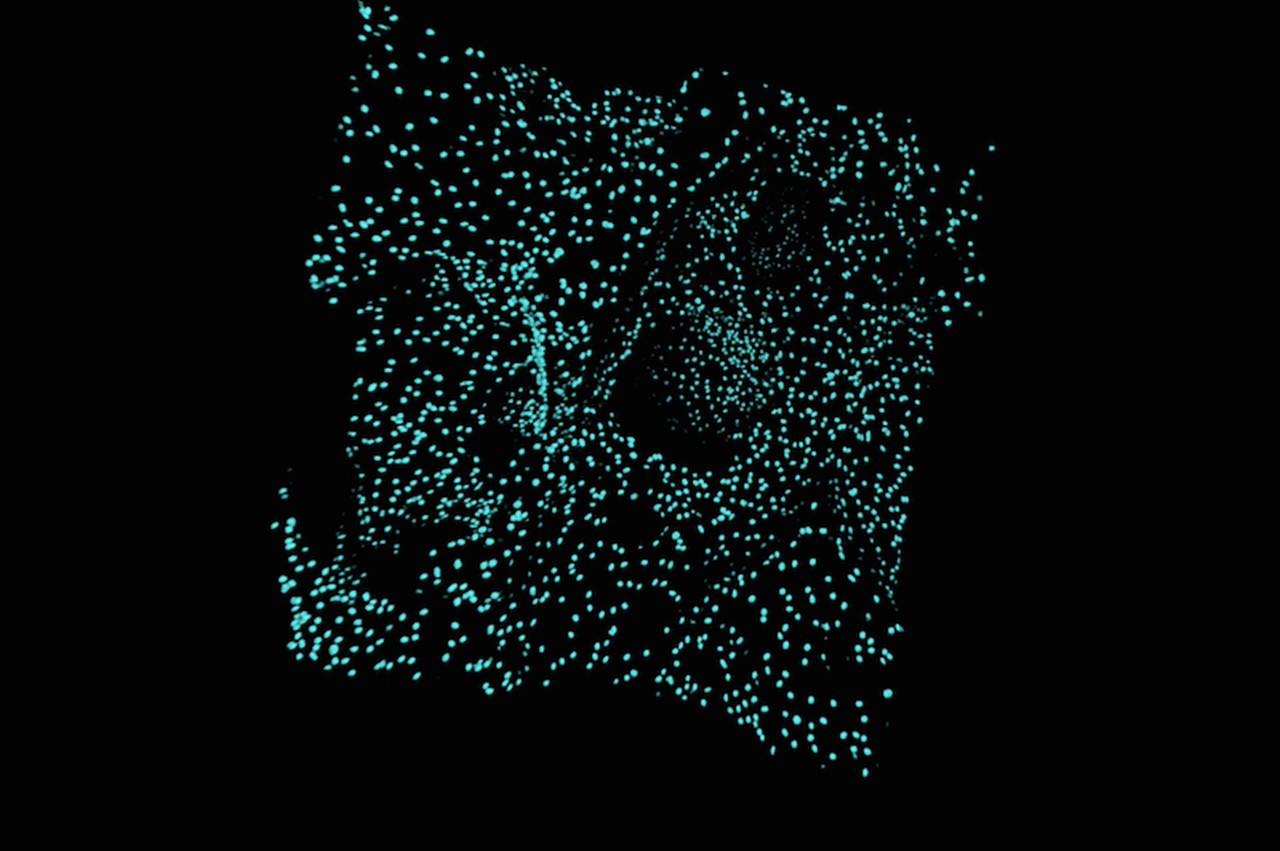

A confocal microscope view of macrophages attached to a ceramic scaffold after six days. (Drexel Imaging Center)

The Drexel research team suspected that the scaffolds’ favorable outcomes must be attributed to macrophages — swallowing white blood cells that digest foreign particles.

Macrophages are the primary cells of the inflammatory response and can rapidly change their behaviors in response to the environment. When the inflammatory response is working properly, it can promote tissue repair, but when gone awry, it can lead to disease. The challenge for the Drexel researchers is to uncover which macrophage phenotype best advances tissue growth, without damaging the healing process.

The researchers found the new ceramic scaffolds caused macrophages to transform into an M2c phenotype, meaning they express genes associated with remodeling. This behavior was not seen in the scaffolds that have been approved to be used in humans. Their findings also showed that macrophages must be in direct contact with the scaffold in order to regenerate tissue.